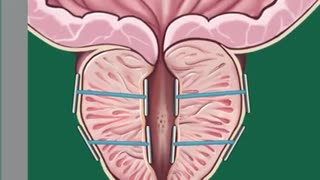

2 years agoUnusual Prostate Technique Doctor's Are Raving About Leads To Prostate Shrinkage